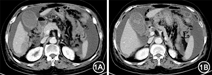

患者女,65岁。主因"腹部胀痛11 d"于2016年1月入院。患者11 d前无明显诱因自觉全腹部胀痛,以下腹部为主,后逐渐加重,伴恶心呕吐,无腹泻。遂于当地医院就诊,查血淀粉酶:466 U/L。上腹部CT平扫示:腹腔多发肿大淋巴结;两侧胸腔积液及腹腔积液。当地医院以"急性胰腺炎"收住入院,并予禁食、抑酸、抑酶、补液等对症支持治疗。患者自觉腹部胀痛逐渐加重,且血清淀粉酶持续为较高水平,遂转入我中心就诊。既往史:2013年5月因卵巢癌行"全子宫切除+左侧附件切除+盆腔部分腹膜切除+盆腹腔肿瘤病灶切除+腹主动脉旁淋巴结清扫+大网膜切除+阑尾切除+直肠部分切除"术,术后于当地医院规律化疗7次(具体不详)。入院体检:神清,体温37.1 ℃,脉搏99次/min,呼吸18次/min,血压140/85 mmHg(1 mmHg=0.133 kPa);中下腹部见一长约20cm手术瘢痕,下腹部压痛(+),无反跳痛及肌紧张,未及包块,肝脾肋下未触及,肝区、双肾区无叩痛,Murphy征(-),移动性浊音阳性,肠鸣音3次/min。入院后行增强CT示:卵巢癌伴腹腔多发转移术后改变;胃窦下方多发结节影及下腹部腹膜增厚,考虑转移可能;腹腔大量积液,盆腔少量积液(图1)。实验室检查:血清淀粉酶404.5 U/L(正常值0~110 U/L),尿淀粉酶3 230 U/L(正常值0~800 U/L),血脂肪酶59.8 U/L(正常值0~60 U/L),C反应蛋白54.32 mg/L,CA125为2 425 U/ml,血脂以及血钙未见异常。结合患者既往卵巢癌病史、增强CT见肿瘤广泛转移证据、CA125明显升高、血淀粉酶升高但脂肪酶正常,考虑其持续高淀粉酶血症以及腹腔积液由卵巢癌广泛转移所引起。告知家属后遂转至肿瘤科进一步化疗。

对于本例患者,存在腹部胀痛,恶心呕吐,血淀粉酶升高,CT检查提示腹腔大量积液,似乎容易误诊为急性胰腺炎。然而,急性胰腺炎时,升高的血淀粉酶多在3~4 d后恢复正常,一般不超1周,且仔细观察两次CT结果发现,患者的胰腺基本形态正常,胰管无扩张征象(图1)。此外,本例患者血脂肪酶正常,也从另一侧面证实高淀粉酶血症并非由急性胰腺炎所致。1930年Cherry和Crandall第1次将血脂肪酶用于诊断急性胰腺炎。由于其半衰期更长,胰腺炎时其持续升高的时间长达8~14 d,灵敏度和特异度更好,目前认为其对于急性胰腺炎诊断的准确度要优于淀粉酶[12]。不可否认的是,脂肪酶的诊断效能同样存在局限性,正如Hameed等[13]在关于高脂肪酶血症的系统评价中指出,一些非胰腺疾病也可导致脂肪酶升高。然而,脂肪酶对于急性胰腺炎的阴性预测值接近100%,目前各大数据库能够搜索到的血脂肪酶正常的急性胰腺炎的病例报道极少[14]。本例血脂肪酶正常而淀粉酶持续较高,既往有明确的卵巢癌手术史、CT提示卵巢癌广泛转移而无胰腺炎征象,CA125明显升高,因此排除急性胰腺炎诊断,考虑血淀粉酶升高由卵巢癌所致。